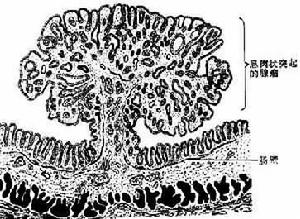

1.腫瘤性息肉

包括管狀腺瘤、絨毛狀腺瘤、混合型腺瘤。其中管狀腺瘤最多見,無蒂腺瘤的癌變率較有蒂腺瘤高,腺瘤越大,癌變的可能性越大,腺瘤結構中絨毛狀成分越多,癌變的可能性越大。